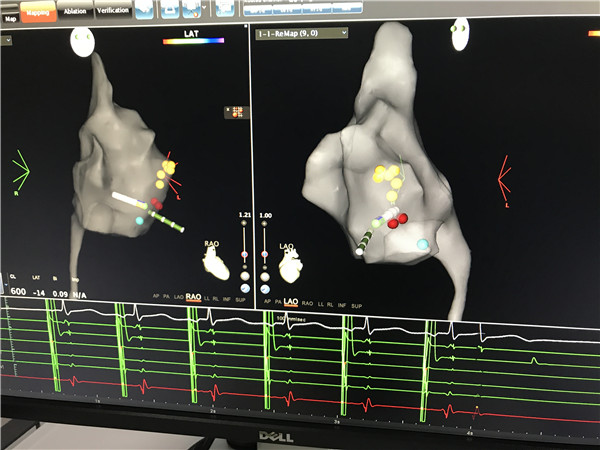

6月28日,心血管病院在郑强荪院长的带领下采用Carto三维标测成功进行顽固性室性早搏(简称室早)及阵发性室上性心动过速(简称室上速)的射频消融治疗,两项治疗均为我院首例。全程手术射线量极低,真正实现了“绿色消融”。

54岁的冯先生4年来反复出现心悸、胸闷,行心电图示频发室早、室早三联律,曾行冠脉造影血管未见明显狭窄,曾服用多种抗心律失常药症状控制不佳,早搏仍持续存在。入院后行动态心电图示室性早搏3万余次。患者走访多家医院均建议行射频消融治疗,但其由于担心手术复杂,并发症多及X射线带来的危害,一直拒绝手术治疗而慕名前来我院。心血管病院郑强荪院长收治患者后决定在三维标测下进行室早射频消融手术。6月28日,郑强荪院长、薛嘉虹副主任医师、王新宏主治医师组成的电生理团队采用Carto三维电解剖标测进行指引下行导管消融。手术过程中通过导管操作能准确建立心脏电解剖图,整个消融过程能够通过三维系统监测导管的位置,避免因消融导管移位而导致的并发症,大大提高手术安全性。整个过程仅仅用时30余分钟就顺利消融成功,全程射线量极低,完成我院首例频发室性早搏“绿色”射频消融手术。术后患者症状消失,室性早搏消失。此项技术不仅根治了患者多年的顽疾,而且以后不用再服抗心律失常药,治疗效果显著。

室早三维图

室上速三维图

35岁的任先生和49岁的王女士均因”阵发性室上性心动过速”入院,平日均有阵发性心慌的症状,发作时心率均达到160-200次/分。两位患者经心脏电生理检查均为房室结双径路导致的室上速。导管射频消融术就是把异常传导径路射频消融。该手术由郑强荪院长、李永勤副主任医师、薛嘉虹副主任医师进行,在三维导航仪引导下,从任意角度观察心腔内各导管空间位置,调整射频导管,标测靶点(病灶)。随后,射频导管释放能量,击中靶点,宣布射频消融获得成功,实现我院首次在三维标测下的室上速射频消融术。整个消融术过程中术者没有踩一脚透视,X光机处于闲置状态,达到了零射线的预定目标。并且用时短,极大降低了手术时间。传统室上速射频消融手术由于在二维下操作,无空间分辨、定位和记忆功能,存在耗费时间长、导管定位不准确、成功率低、并发症多等局限性,射线量常常会很大,所以对患者和医生都可能产生不良的影响。

此三例手术的整个过程均在三维标测系统指引下,免除X线透视,真正实现了“零射线,绿色电生理”,将射频消融由“二维”时代转化为“三维”时代,开启了“绿色电生理”模式。可以最大限度保护了患者及医护人员的健康。心血管病院三维标测下射频消融技术的成功开展实施,给患有快速心律失常(房颤、室早、室速、室上速)的人群带来福音,标志着我院心血管病院对心律失常射频消融治疗的诊治水平再上新台阶,也标志着我院电生理水平已处于国内先进水平。